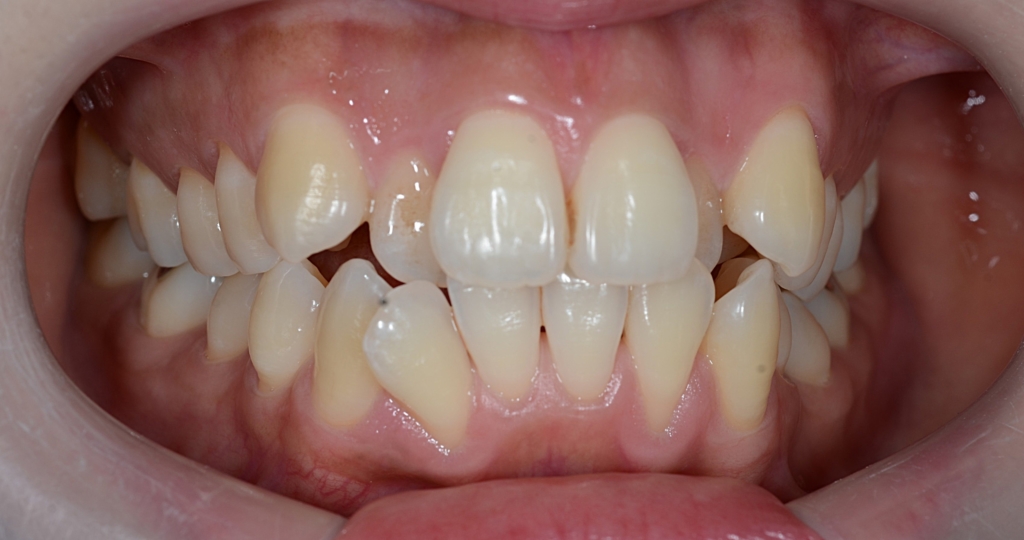

【Before】

#1.顎と歯の不調和による叢生(重度)

#2.上顎前突(奥歯の噛み合わせ)

と診断しました。